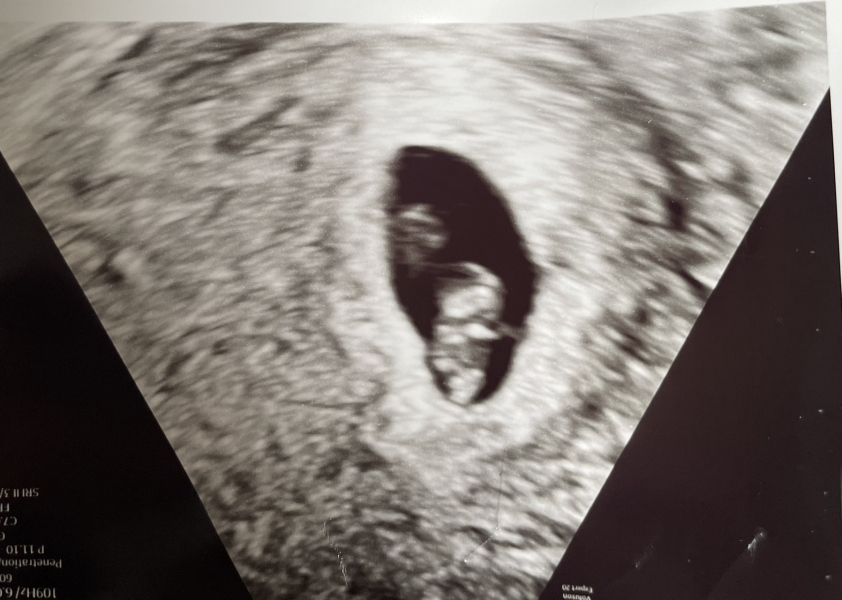

I'm 7 weeks today and did have my first EPU scan today for the new pregnancy, and saw a beautiful little blob measuring 7 weeks exactly. They pointed out the heart, brain and little limb buds. All we can do is our very best and keep pushing for the care we need.

Mines approx 23rd sept however I will be collecting sec so maybe 14th Sept not sure yet till proper datimg scan. Mu two other children are goimg to be 10 on 13th Sept and 12 on 24th Sept. So seems Sept is the month. Lovely news @KittyFantastica ypir scan is so clear..xx